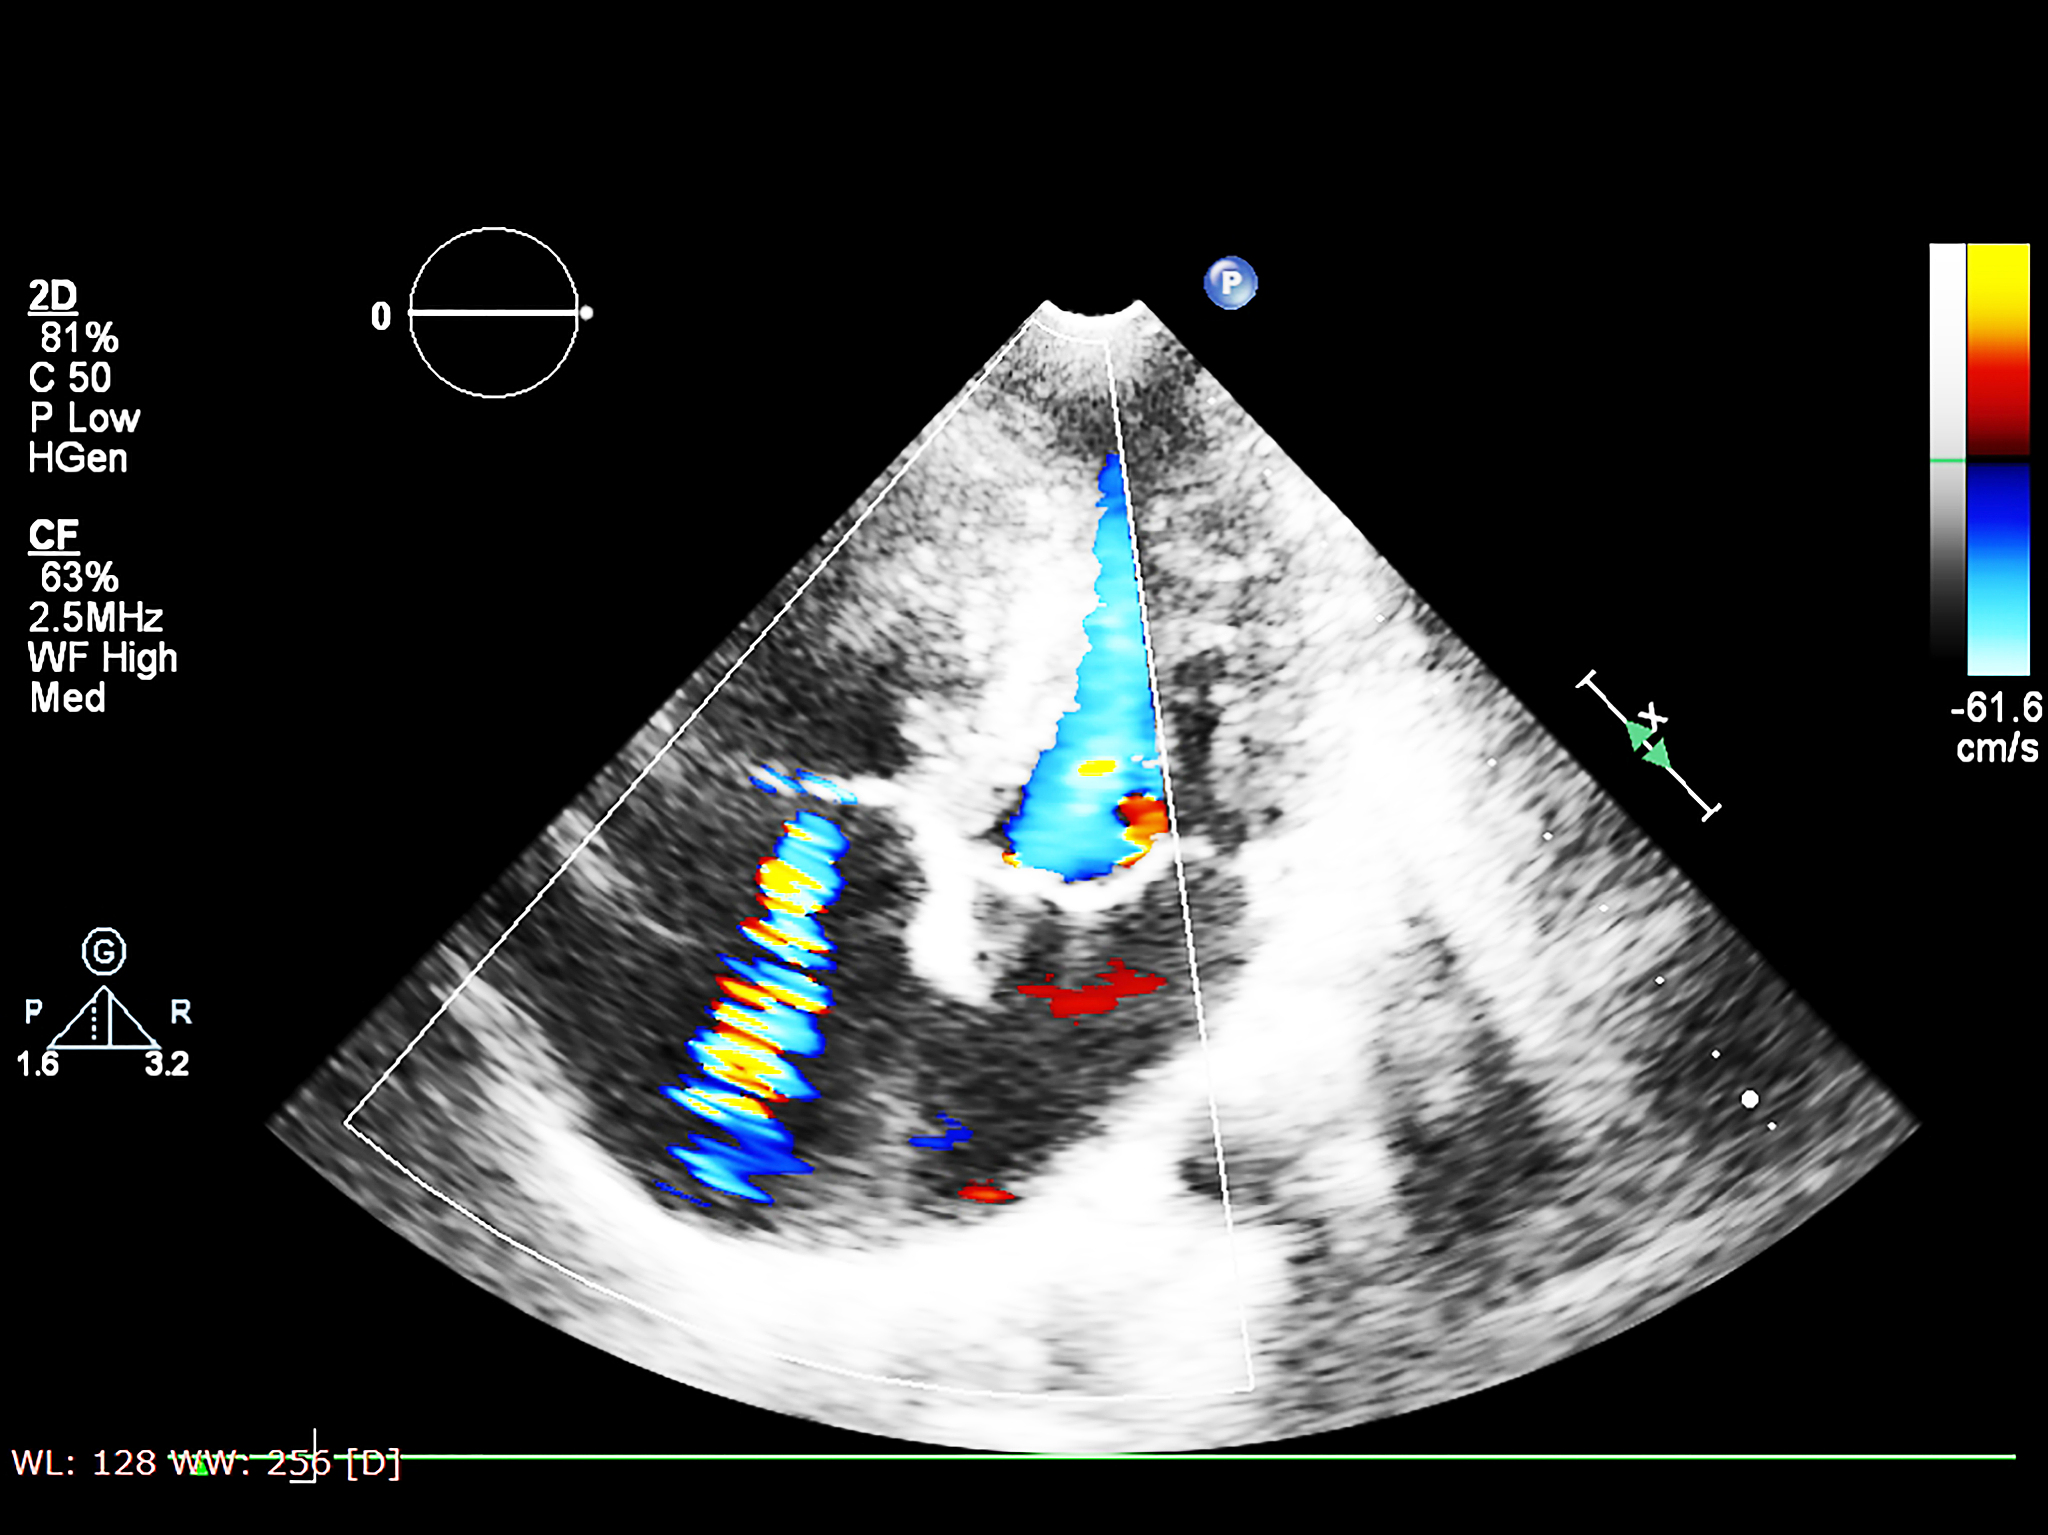

腔内超声造影技术近年来在胆道疾病诊断和治疗中得到广泛应用。该技术利用微泡造影剂增强超声信号,为胆道疾病的诊断和治疗提供了更加清晰、准确的影像信息。

总之,腔内超声造影技术在胆道疾病诊断和治疗中具有重要的应用价值,它能够提高诊断准确率、减少手术并发症、缩短手术时间,为患者提供更加精准的医疗服务。

腔内超声造影在胆道疾病中的应用:精准诊断与治疗的新技术